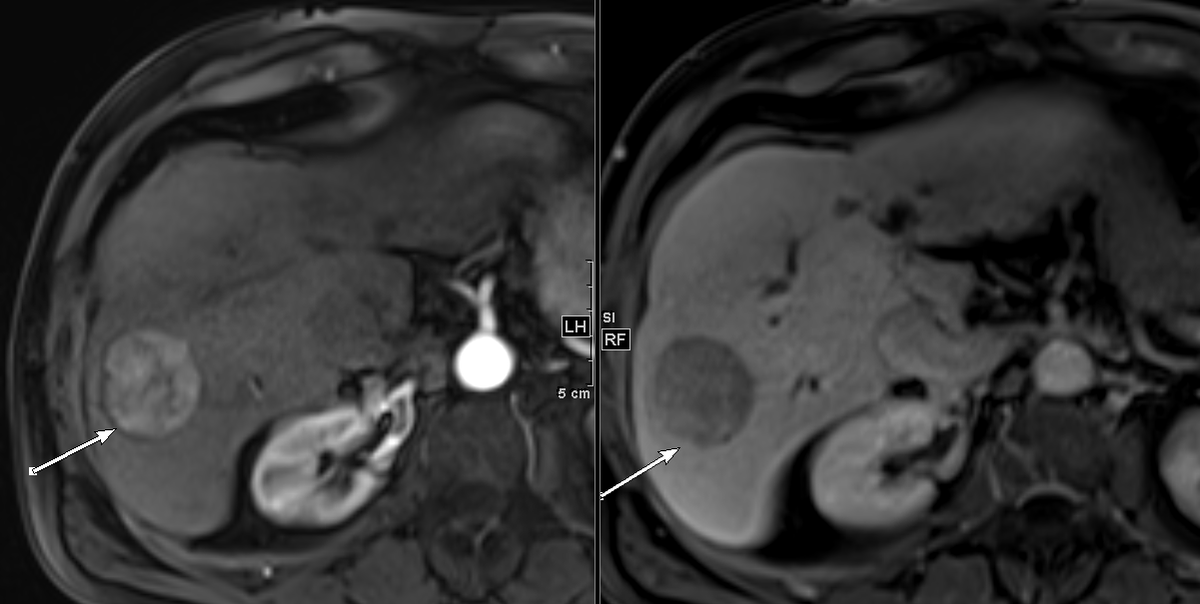

My perfect sphere HCC TACE

#radreshttps://twitter.com/bonesz/status/1207425485078224897 …